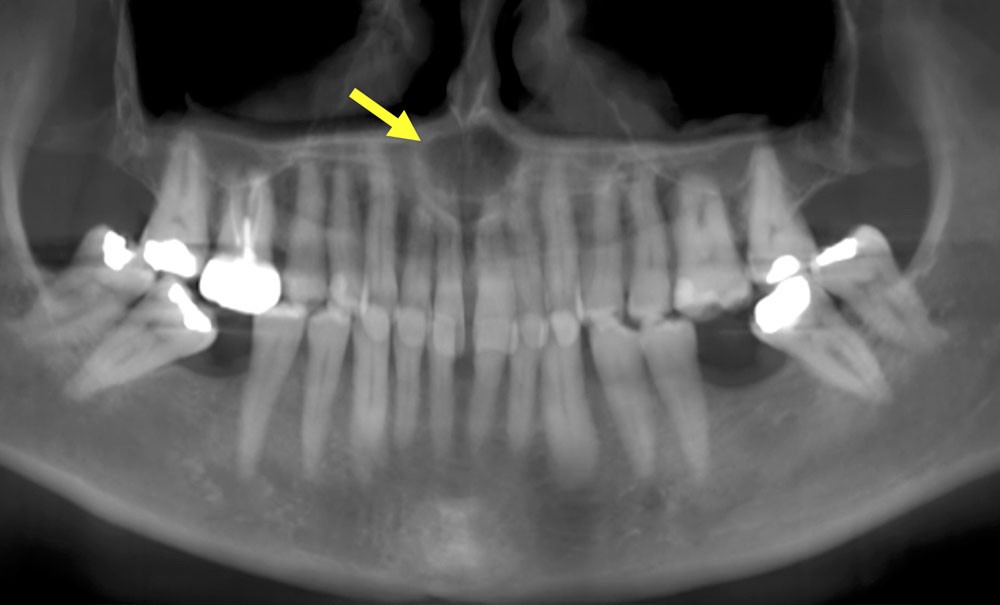

- Centré sur la ligne médiane de la portion antérieure du palais.

- Lésion ostéolytique radio-claire.

- Homogène et bien délimitée.

- Uni-loculaire (fig. 3), pouvant présenter un aspect caractéristique de « cœur de carte à jouer ».

- Diamètre moyen des lésions de 2 cm.

- Lorsque le kyste devient volumineux : possibilité de fenestrer la corticale palatine et/ou vestibulaire. Il peut également se développer dans les fosses nasales ou être associé à des résorptions radiculaires (moins de 25% des cas) (fig. 4).

- Plus rarement, extension latérale jusqu’aux prémolaires de façon asymétrique (fig. 5).